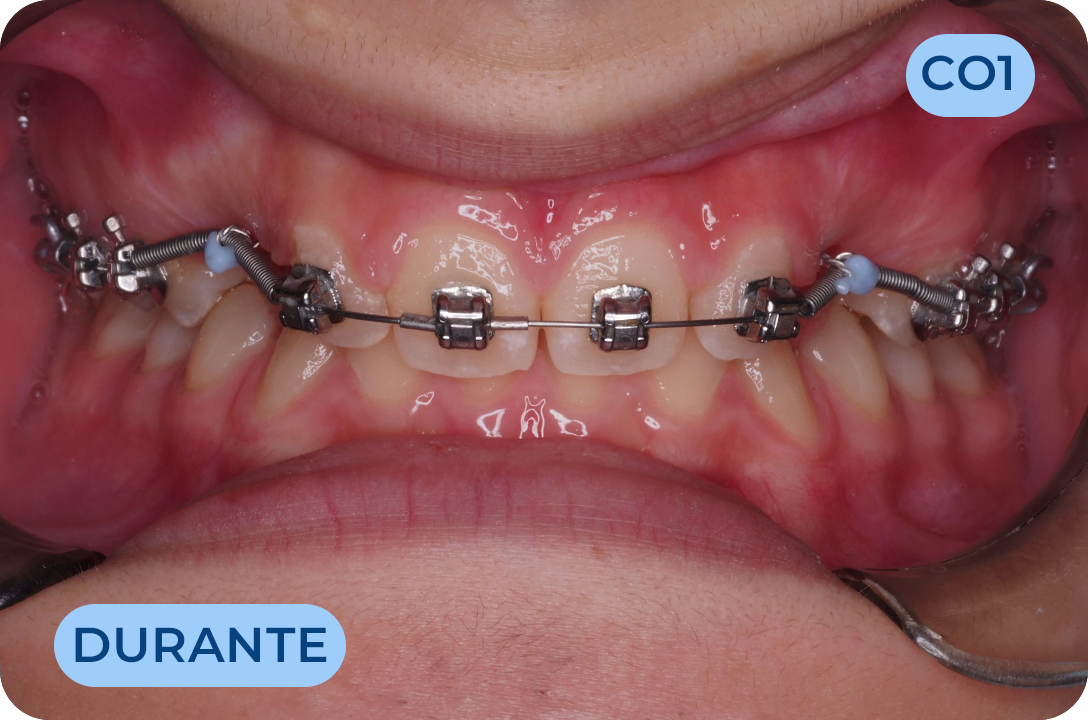

Ortodontia

É a especialidade da Medicina Dentária que se debruça sobre o estudo e correção das más posições dentárias e dos maxilares. Atualmente é possível tratar pacientes de todas as idades, no entanto a 1ª consulta deve ser realizada ainda na infância para intercetar eventuais problemas de desenvolvimento esquelético e funcional.